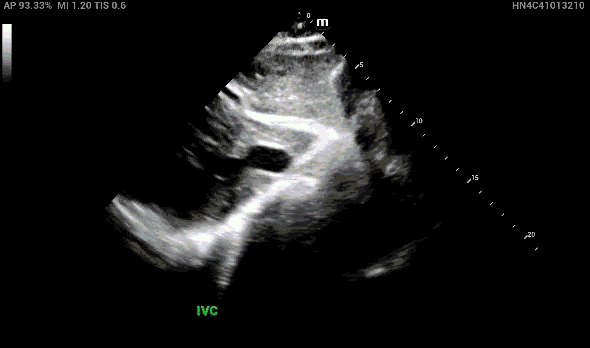

In the parasternal long view, the right ventricular outflow tract (RVOT), aortic root and left atrium should all be about equal in size (rule of thirds), however the RVOT looks enlarged in comparison.